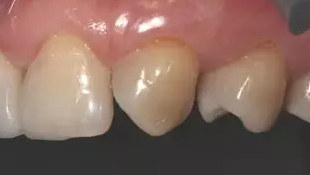

術前上前牙正面照

病例分享|復合樹脂微創(chuàng)美學修復關閉上前牙間隙

術前上前牙右側面照